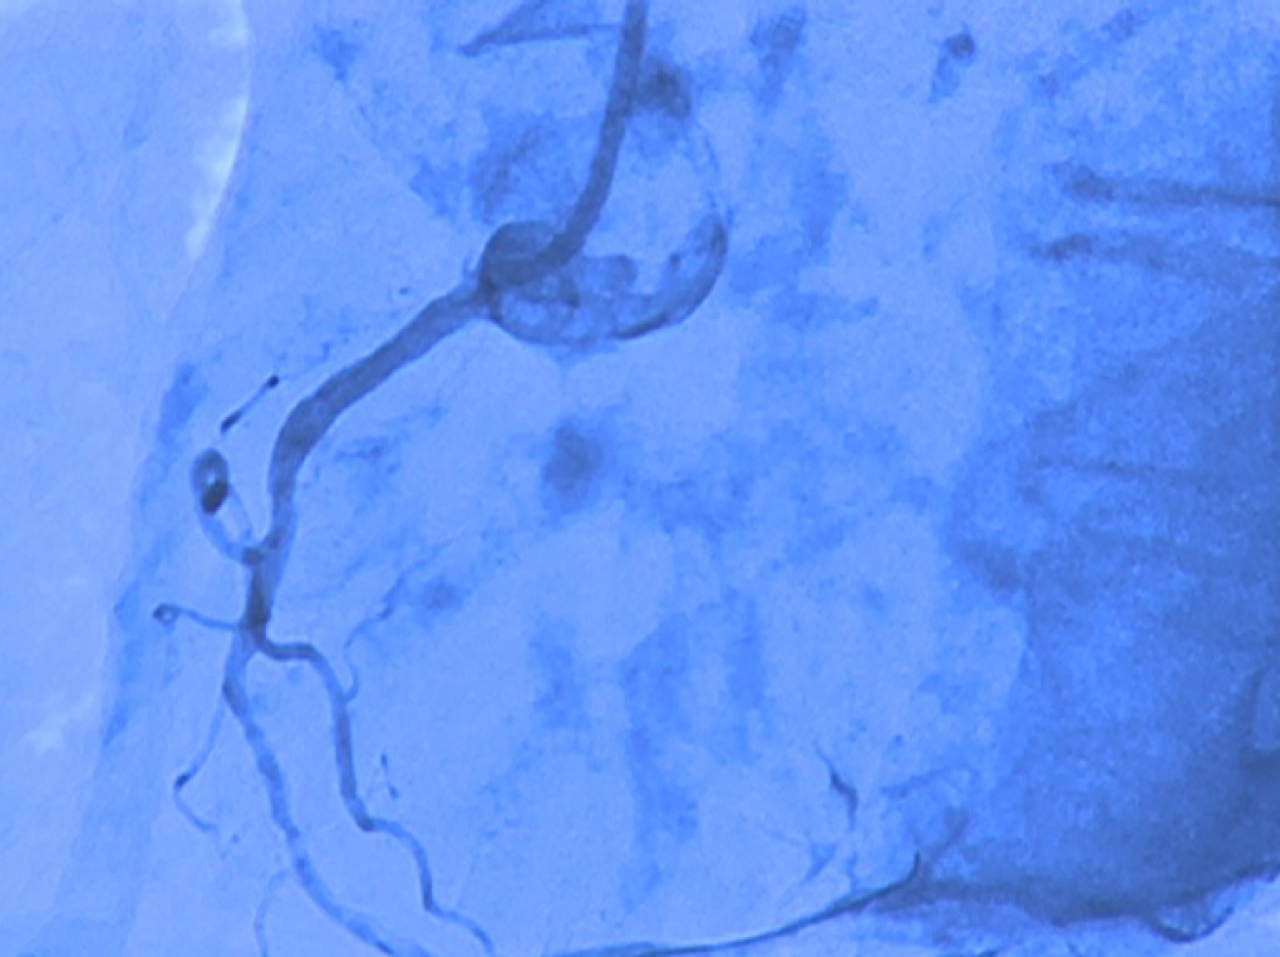

Néhány éve 24 órás ügyeletet is működtetnek, így az infarktusos betegek halálozása a felére csökkent Szabolcs-Szatmár-Bereg megyében. Évente átlagosan 1500 katéterezést végeznek el a Jósa András Oktatókórházban, év végére pedig már a tízezredik beavatkozást is végrehajtották. A professzor kiemelte, az ellátás spektrumát szeretnék tovább bővíteni egy olyan központ létrehozásával, ahol valamennyi érrendszeri megbetegedés gyógyítására, korszerű terápiájára lehetőség van. A tudományos ülésen az invazív, vagyis műtéti eljárásokról is tanácskoztak a szakemberek. A kórházban például a koszorúér tágítását korábban egy stent, azaz egy fémháló beültetésével végezték az orvosok. Az eszközt manapság már gyógyszerrel együtt használják, így pedig a visszaszűkülés arányát sikerült 20 százalékról 5 százalékra csökkenteni.